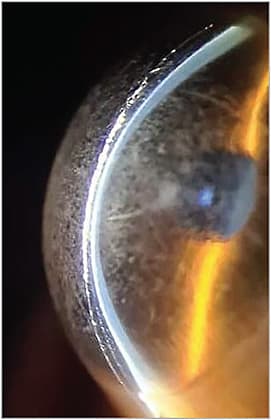

The second issue in this case is the complete loss of central clearance where the lens is now resting on the cornea. We can see that this eye has undergone radial keratotomy (RK), which is the third leading indication (after keratoconus and pellucid marginal degeneration) for scleral lens fitting.1 Numerous studies have shown that lenses lose central clearance (“settling”) over time. One found that lenses 16.5mm in overall diameter (n = 15) settled an average of 76 microns (± 8µm) over an eight-hour period.4 Seventy-five percent of the settling occurred in the first two hours.4 Other studies, with lenses from various manufacturers, found rates of settling over eight hours varied as well (e.g., 113.7µm, 133.7µm, and 88.1µm).5 With this in mind, when ordering, the recommendation is to build in enough vault to account for the lens sinking into the conjunctiva over time.6